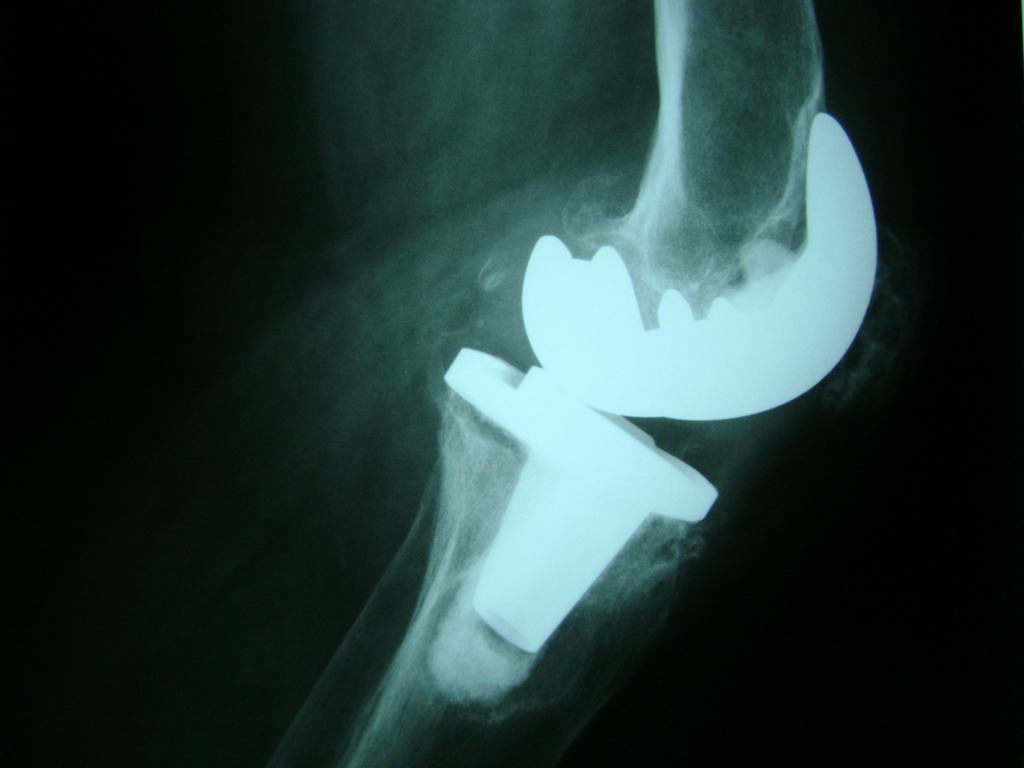

Cirugías de Codo - Rodilla

La artroscopia de rodilla es un cirugía en el cual la estructura interna de la articulación es examinada ya sea para realizar un diagnostico o para realizar un tratamiento, este procedimiento se realiza utilizando un instrumento parecido a un pequeño tubo llamado artroscopio.